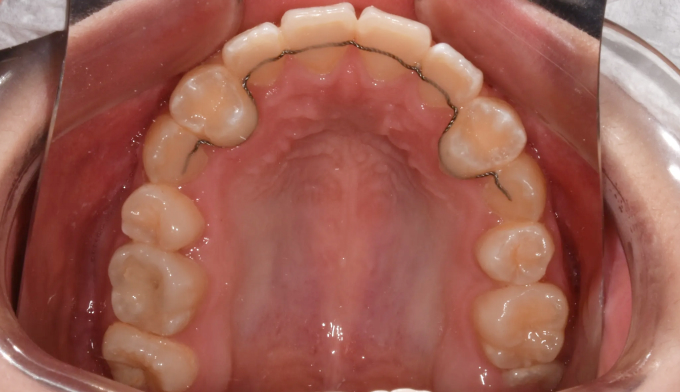

좁은 위턱을 확장하여 치아를 배열할 공간을 만들어주었고, 이 공간을 이용해 치아를 배열합니다.

총 치료기간은 26개월 입니다.

아이의 성장기에는 주기적으로 치과에 내원하여 치아의 맹출 방향이 올바른지, 방해되는 요소는 없는지 확인하여야 합니다.